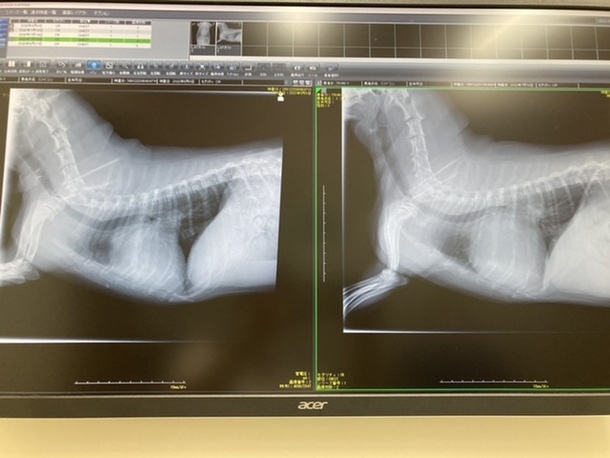

今日、しん動物病院へ抜糸と検査に病院へ行きました。左側が今日撮りました画像です。

心臓の腫れが引いたお陰で咳が出ないそうです。

腎臓の数値が高いそうで、下げる薬が追加になりましたが先生からは問題ないでしょうとの言葉を頂きホッとしております。